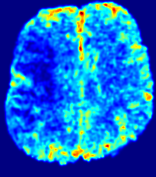

LesionRefer to captionRefer to captionRefer to captionRefer to captionRefer to captionRefer to caption𝐕rgbsubscript𝐕𝑟𝑔𝑏{\bf{V}}_{rgb}Refer to captionRefer to captionRefer to captionRefer to captionRefer to captionRefer to caption𝐕2subscriptnorm𝐕2{\|\bf{V}}\|_{2}Refer to captionRefer to captionRefer to captionRefer to captionRefer to captionRefer to captionRefer to caption3.53.53.52.82.82.82.12.12.11.41.41.40.70.70.70.00.00.0(mm/s)𝑚𝑚𝑠(mm/s)D𝐷DRefer to captionRefer to captionRefer to captionRefer to captionRefer to captionRefer to captionRefer to caption0.0200.0200.0200.0160.0160.0160.0120.0120.0120.0080.0080.0080.0040.0040.0040.0000.0000.000(mm2/s)𝑚superscript𝑚2𝑠(mm^{2}/s)Slice #1Slice #2Slice #3Slice #4Slice #5Slice #6

Figure 3: PIANO feature maps for one stroke patient, where the lesion is located in the left hemisphere. Top row: segmented stroke lesion region (white) on different slices, obtained from ISLES 2017. The corresponding slices for the PIANO feature maps are shown in the following rows.

For a better insight into an estimated velocity field 𝐕𝐕{\bf{V}} and diffusion field 𝐃𝐃{\bf{D}}, we compute the following maps: (1) 𝐕rgbsubscript𝐕𝑟𝑔𝑏{\bf{V}}_{rgb}: Color-coded orientation map of 𝐕=(Vx,Vy,Vz)T𝐕superscriptsuperscript𝑉𝑥superscript𝑉𝑦superscript𝑉𝑧𝑇{\bf{V}}=(V^{x},V^{y},V^{z})^{T}, obtained by normalizing 𝐕𝐕{\bf{V}} to unit length and mapping its 3 components to red, green, blue respectively; (2) 𝐕2subscriptnorm𝐕2\|{\bf{V}}\|_{2}: 222 norm of 𝐕𝐕{\bf{V}}; (3) D𝐷D: scalar field in Eq. 5.

Fig. 3 and Fig. 4 show the PIANO feature maps estimated from two ISLES 2017 patients: all are highly consistent with the lesion in both cases. Details of the blood flow trajectories are revealed in 𝐕rgbsubscript𝐕𝑟𝑔𝑏{\bf{V}}_{rgb} by the ridged patterns and the sharp changes of colors in the unaffected (right) hemisphere, while the flat patterns appearing within the lesion provide little directional information about the velocity and indicate low velocity magnitudes. Velocity magnitudes are more directly visualized via 𝐕2subscriptnorm𝐕2\|{\bf{V}}\|_{2}, from which one can easily locate the lesion where 𝐕2subscriptnorm𝐕2\|{\bf{V}}\|_{2} is low. D𝐷D also indicates lower diffusion values in the lesion, though with less contrast potentially due to the fact that it captures the accumulated effect of CA diffusion at the voxel-level.